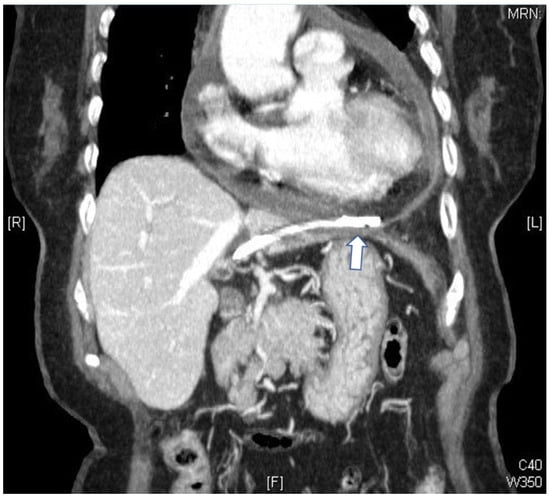

Bacterial Pericarditis Caused by Penetration of a Migrated Biliary Stent from the Lateral Segment of the Liver: A Case Report

2. Case Report